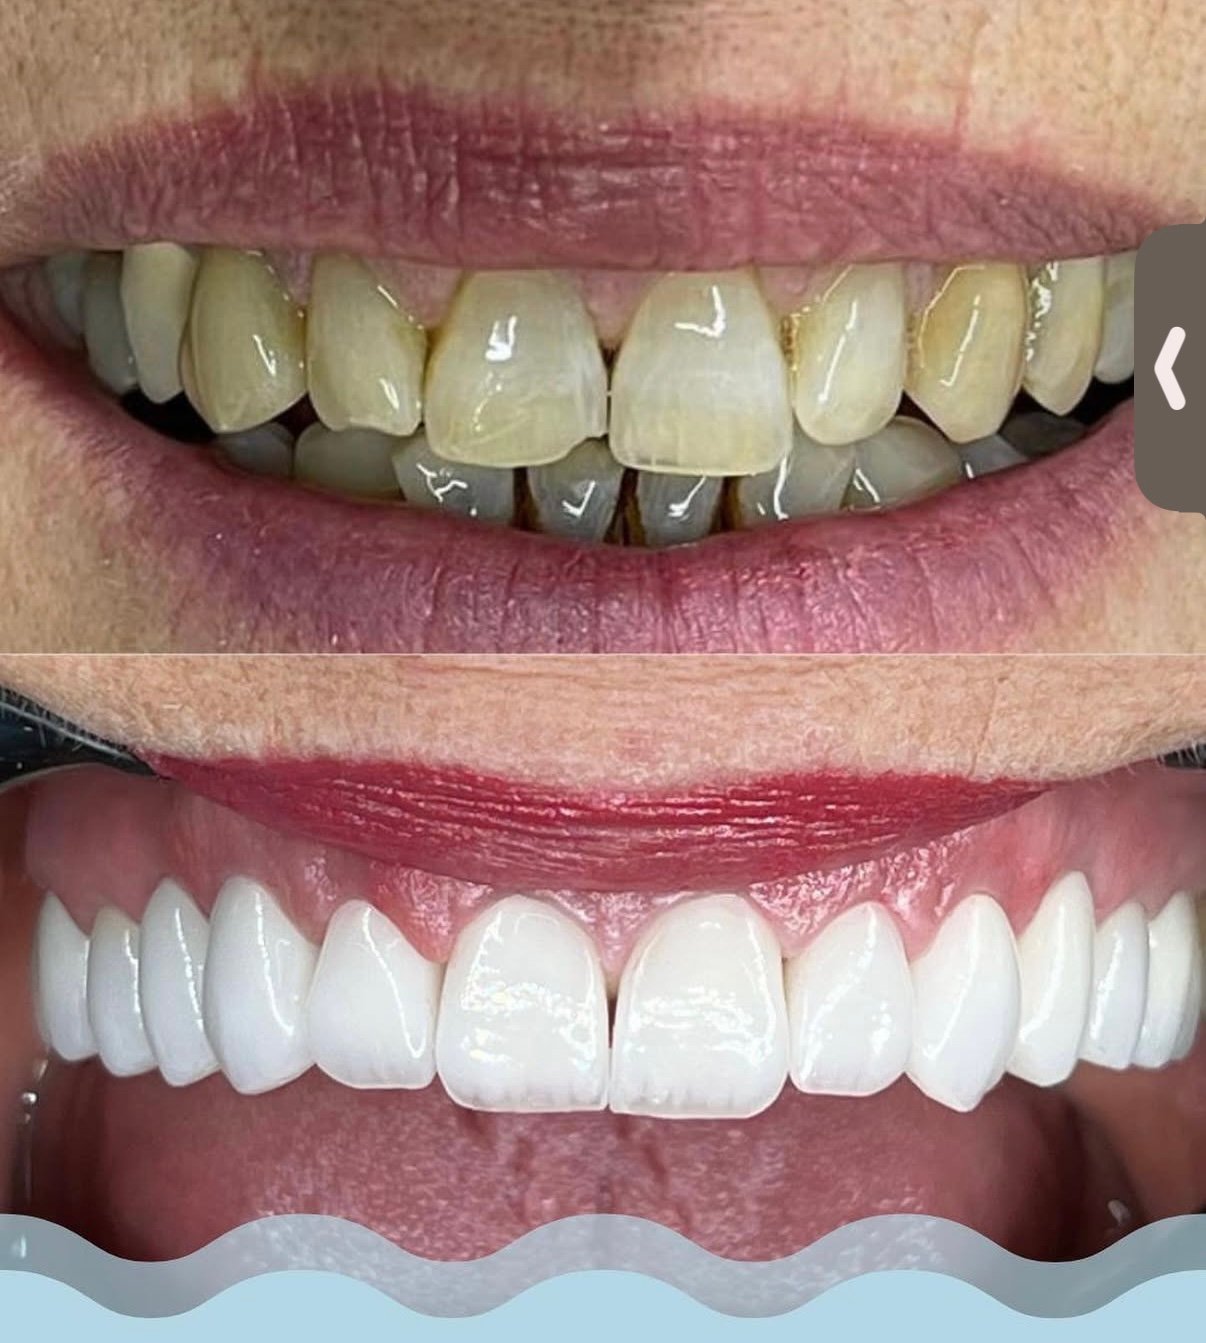

Screenshot